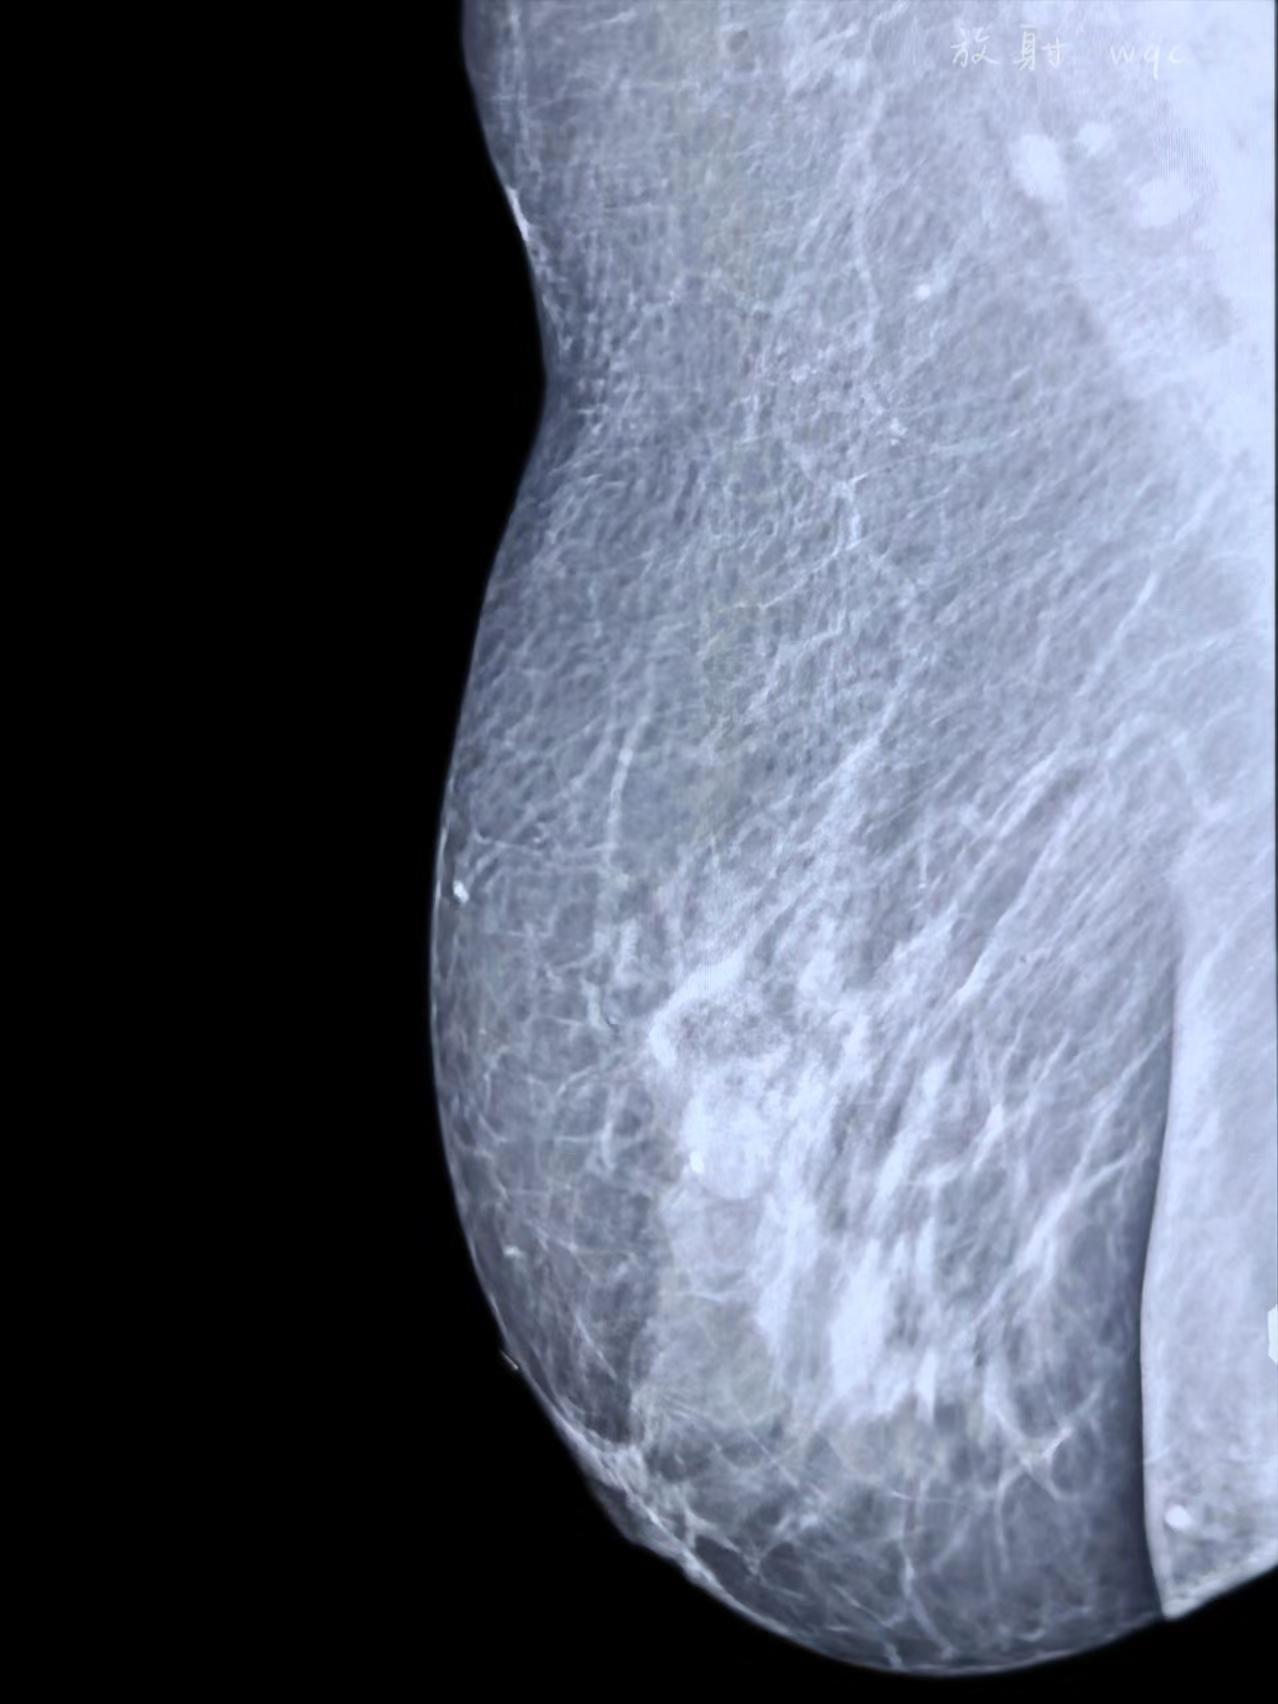

良性还是恶性?

2025-09-12 18:45